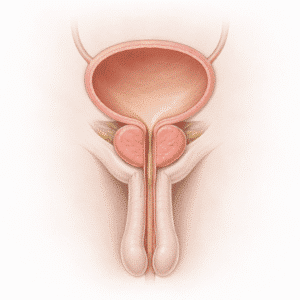

Erectile dysfunction

Understanding Erection Problems Erection problems, also known as erectile dysfunction…

Premature Ejaculation

Understanding Premature Ejaculation Premature ejaculation is one of the most…